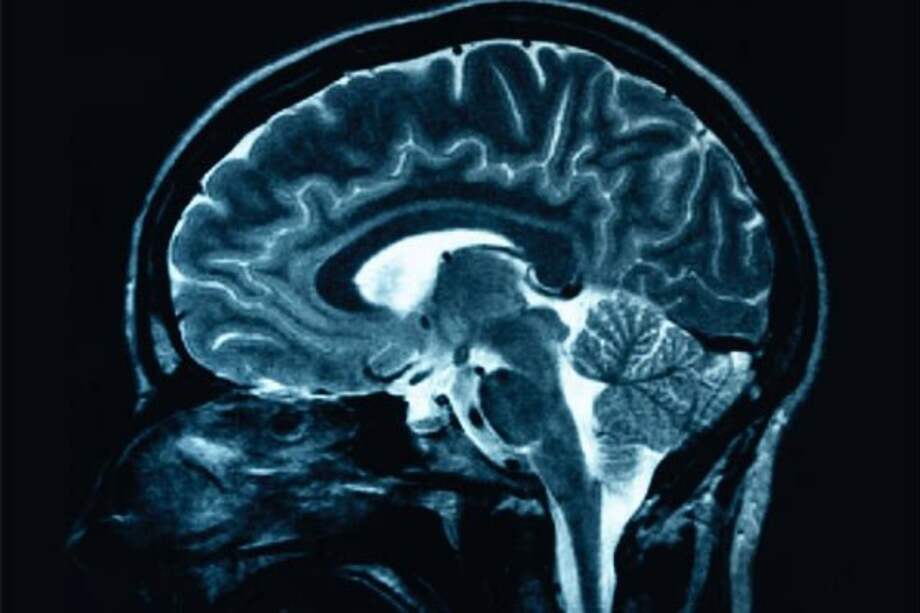

Tener un cerebro más grande no es una garantía de tener un QI más alto, ya que lo que importa es cómo esté estructurada la materia gris, reveló un extenso estudio que cruza los datos de decenas investigaciones anteriores.

El científico afirmó que el factor decisivo es "la estructura del córtex, el mesencéfalo (el cerebro medio) y el cerebelo, y el hecho de que la materia blanca esté conectada con la materia gris de una forma óptima".